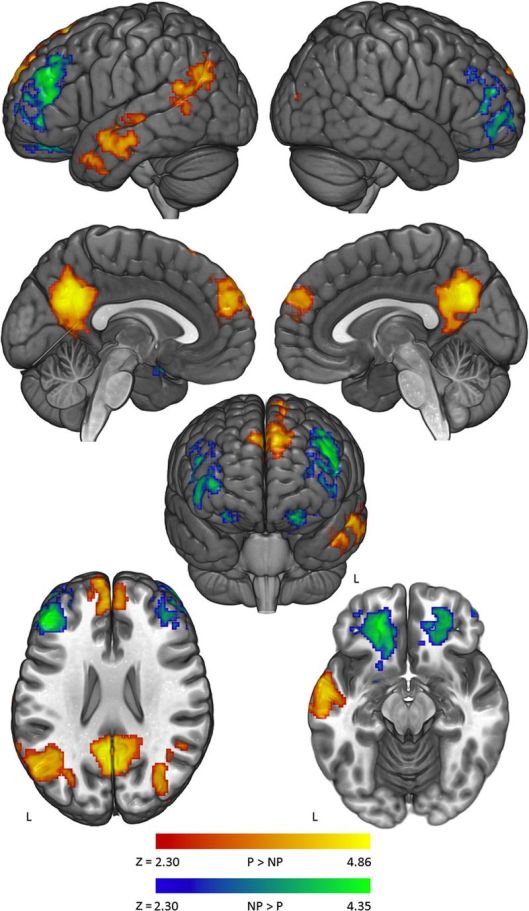

Deep reading activates our brain’s centers for speech, vision, and hearing, all of which work together to help us speak, read, and write. Reading and writing engages Broca’s area, which enables us to perceive rhythm and syntax; Wernicke’s area, which impacts our perception of words and meaning; and the angular gyrus, which is central to perception and use of language. These areas are wired together by a band of fibers, and this interconnectivity likely helps writers mimic and synchronize language and rhythms they encounter while reading. Your reading brain senses a cadence that accompanies more complex writing, which your brain then seeks to emulate when writing.

In an article published in the Journal of Consciousness Studies, researchers reported finding activity in a “reading network” of brain areas that were activated in response to any written material. In addition, more emotionally charged writing aroused several regions in the brain (primarily on the right side) that respond to music. In a specific comparison between reading poetry and prose, researchers found evidence that poetry activates the posterior cingulate cortex and medial temporal lobes, parts of the brain linked to introspection. When volunteers read their favorite poems, areas of the brain associated with memory were stimulated more strongly than “reading areas,” indicating that reading poems you love is the kind of recollection that evokes strong emotions—and strong emotions are always good for creative writing.